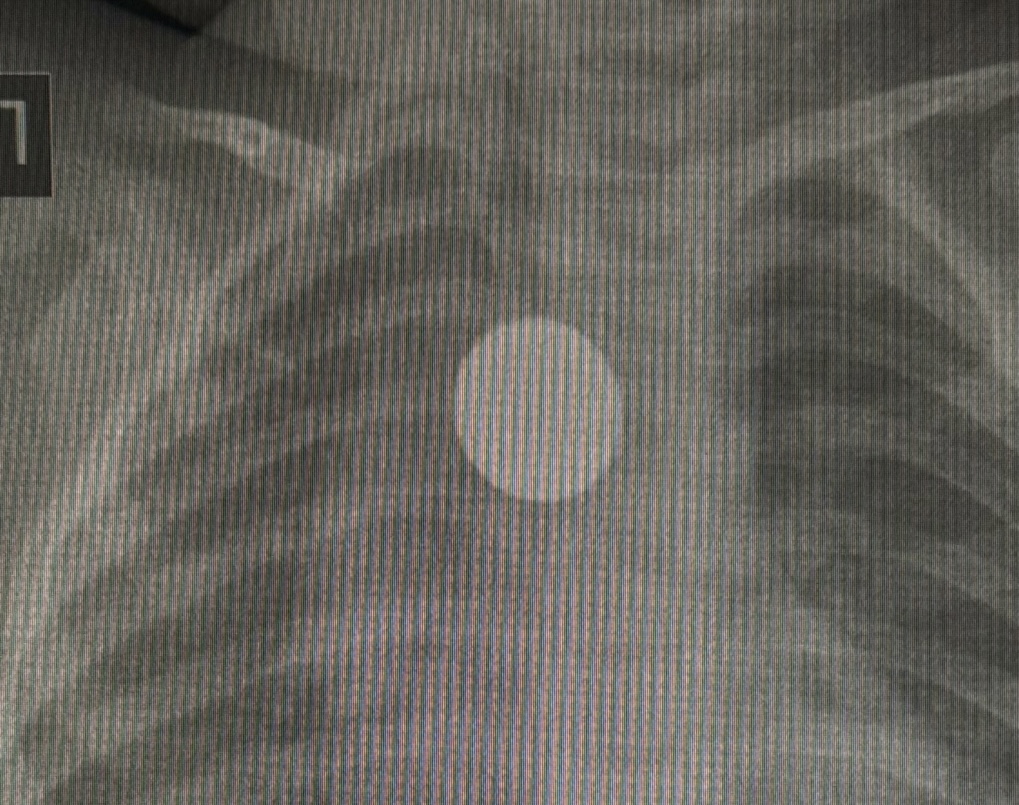

由于孩子持续咳嗽一个月,医生为其拍摄胸部X光片时,意外发现了这枚硬币。

医生发现硬币卡在食道中段,并在全身麻醉下通过内窥镜成功取出。

主刀医生玛丽娅·叶列梅耶娃在取出女童食道中5元硬币的手术中。

图片来源:雅库特共和国医院。